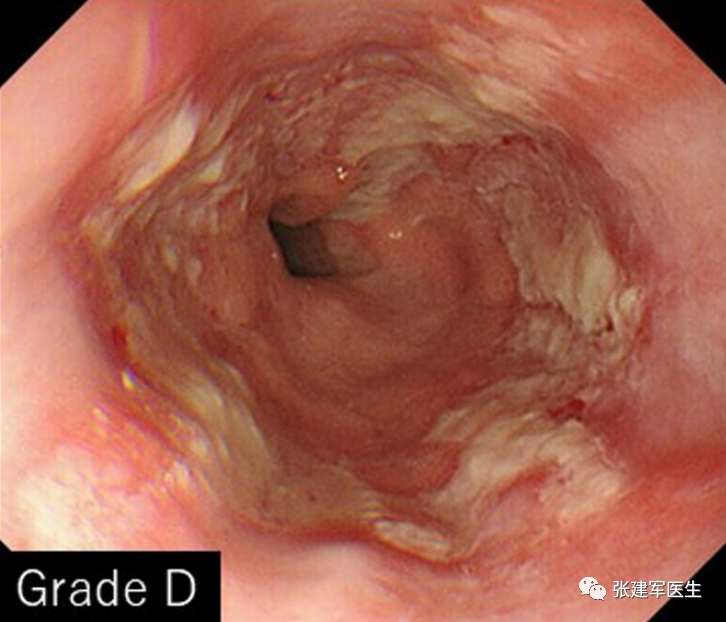

食道炎(Esophagitis),食道中的酸会导致食道内壁发炎。 慢性炎症会导致疼痛、吞咽问题、溃疡甚至出血。

食管狭窄(Esophageal stricture), 慢性炎症会导致食道组织留下疤痕。疤痕组织会干扰吞咽肌肉并导致食道变窄。

胃十二指肠镜检查

能直观评估食管、胃以及十二指肠粘膜状态,诊断糜烂性食管炎及巴雷特食管(Barrett's esophagus),明确食管裂孔疝的大小及类型,确定食管裂孔疝有无扭转。